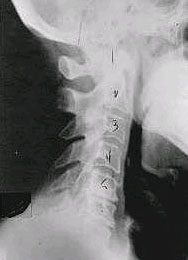

| Phase One Subluxation Degeneration

This X-ray shows Phase One Subluxation Degeneration. Compare this to the X-ray above, and you can see how the normal curve in the spine is lost. In this example, the neck is actually curving in reverse, and the disc spaces have begun to slightly change in shape. Since this is only Phase One Subluxation, you can see that the body of each of the vertebrae (the square part in front) still exhibits clean clear borders. In this patient's case, segmental motion may be abnormal, but overall motion is probably not affected. It is interesting to note that most people with Phase One Subluxation Degeneration have no pain. |

Phase Two Subluxation Degeneration

In this phase, some of the same characteristics of Phase One Subluxation Degeneration can be seen, as well as the loss of normal curvature and position, and a shift in segmental motion. People with Phase Two Subluxation Degeneration begin to display a reduction in their range of motion. X-rays of a Phase Two patient show calcium changes or buildup at certain levels of the spine, which are commonly referred to as spurs or arthritis. Also, the disc spaces between the affected vertebrae are narrower, and appear to be flattening out. |